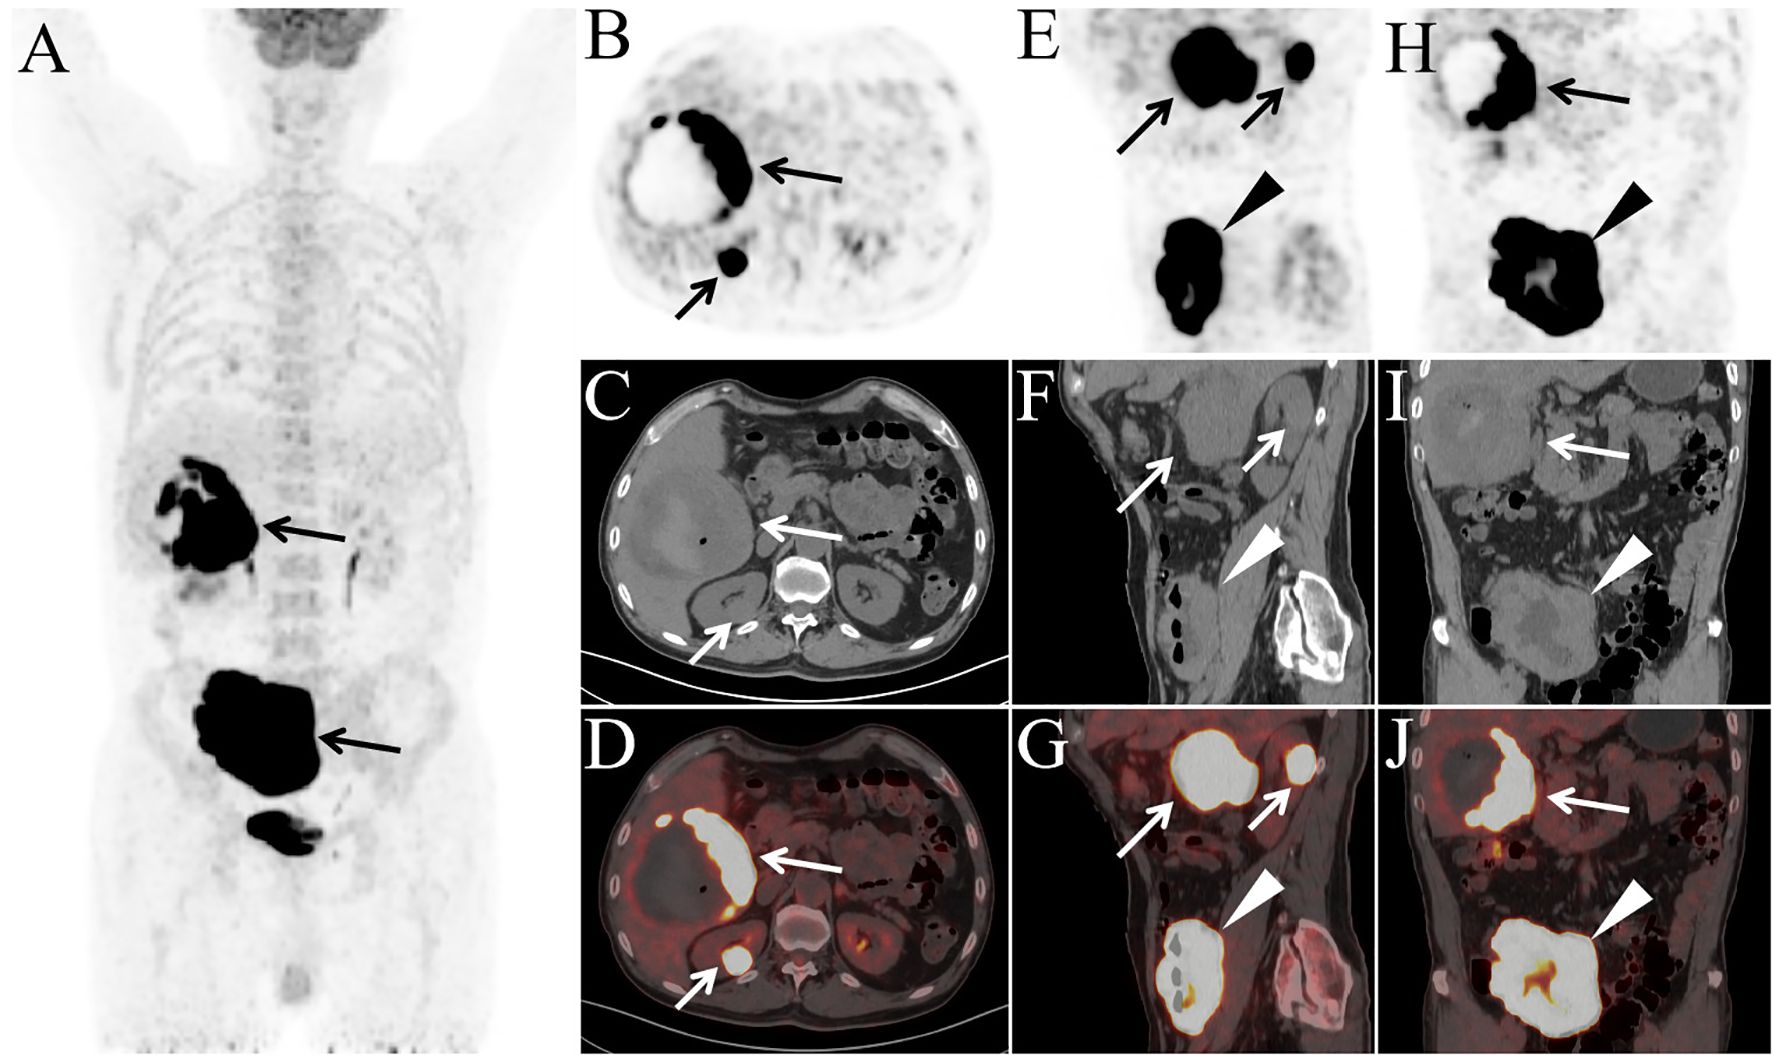

A 78-year-old male presented with abdominal pain and underwent contrast-enhanced CT at an outside hospital, which revealed a large hepatic mass with internal hemorrhage and significant thickening of the ileal wall, both highly suspicious for malignancy. The patient exhibited no B symptoms such as fever, night sweats, or weight loss, and routine laboratory tests, including blood counts, liver and renal function, electrolytes, and tumor markers, were unremarkable. The patient had no significant past medical history and no family history of malignancy. The patient initially received interventional treatment to control hepatic bleeding. After achieving hemodynamic stabilization, an ileal biopsy was performed via colonoscopy, and pathological examination confirmed the diagnosis of diffuse large B-cell lymphoma (Figure 1A). Immunohistochemical staining (Figures 1B, C) showed the following profile: CD20(+), CD79α(+), CD3 (scattered+), CD45RO (scattered+), CD5 (scattered+), CD23(−), Bcl-2 (90%+), Bcl-6 (90%+), C-MYC (50%+), CD10 (+), MUM-1(+), CD56(−), TIA-1(−), P-CK(−), and Ki-67 (90%+). Immunohistochemical analysis revealed positivity for CD20 and CD79α, confirming B-cell lineage. High expression levels of Bcl-2, Bcl-6, and C-MYC, along with a Ki-67 index of 90%, indicated high tumor aggressiveness. The CD10(+)/MUM-1(+) profile suggested a germinal center B-cell (GCB) subtype, supporting the histopathological diagnosis of DLBCL. For disease staging, the patient was referred to our hospital for [18F]FDG PET/CT. [18F]FDG was administered intravenously at a dose of approximately 5.5 MBq/kg, and imaging was performed using a United Imaging uMI 550 PET/CT system. PET/CT (Figures 2A–J) revealed markedly increased FDG uptake in both hepatic and ileal lesions. Additionally, PET/CT identified a slightly hyperdense nodule in the right kidney—missed on prior CT—with significantly elevated FDG metabolism. The patient underwent biopsies of both the liver and kidney lesions at another hospital prior to receiving further treatment, and the pathological results confirmed the diagnosis of lymphoma. This effectively ruled out the possibility of multiple primary malignancies.The final stage of lymphoma was determined to be stage IV, with an International Prognostic Index(IPI) score of 3. Three months later, the patient completed four cycles of R-CHOP chemotherapy. Follow-up [18F]FDG PET/CT (Figures 3A–J) demonstrated significant reduction in the size of hepatic, ileal, and renal lesions with markedly decreased FDG metabolism, indicating an excellent treatment response. The patient's disease timeline is shown in Table 2.

Figure 2

Medical imaging panels showing PET and CT scans highlighting areas of abnormal tissue or lesions, indicated by arrows and a triangular marker. Panels A, B, E, and H display PET scans with dark areas; panels C, F, and I present CT scans with arrows pointing to specific regions of interest. Panels D, G, and J are PET/CT fusion images. The triangular marker highlights notable features within the scans.

Figure 2. The patient underwent PET/CT examination for staging [(A) MIP; (B, E, H) PET; (C, F, I) CT; (D, G, J) PET/CT]. MIP image shows abnormally increased FDG uptake in the right upper and lower abdominal regions (A, arrows). Axial (B–D), sagittal (E–G), and coronal (H–J) PET/CT images demonstrate a large mass in the posterior segment of the right hepatic lobe measuring 11.0 cm × 10.2 cm × 10.5 cm (B–J, long arrows), a slightly hyperdense nodule in the right kidney measuring 2.6 cm × 2.2 cm × 2.6 cm (B–G, short arrows), and diffuse thickening of the ileal wall with a maximum wall thickness of 4.3 cm (E–J, arrowheads), all exhibiting markedly elevated FDG uptake (SUVmax: hepatic lesion, 32.3; renal lesion, 34.1; ileal lesion, 34.3). Central necrosis, hemorrhage, and a small amount of intralesional gas were observed within the hepatic mass. Notably, there was no evidence of lymphadenopathy or abnormal FDG uptake in any lymph nodes throughout the body.